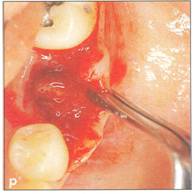

Fi 545e45f g 5-10 Stabilization of the donor tooth. The donor tooth has been splinted to the adjacent tooth with twisted wire and selfcured composite resin after etching and bonding. Fi 545e45f g 5-1 p After transplantation. |

|